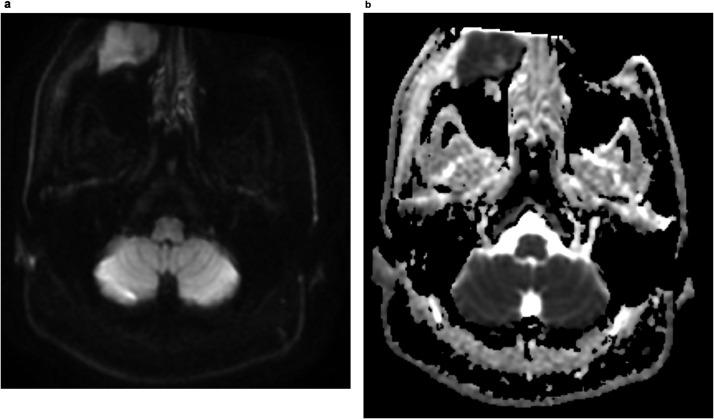

Lymphomas are the most common nonepithelial malignancy in the head and neck region. Among these, non-Hodgkin Lymphoma (NHL) is the most prevalent, and diffuse large B-cell lymphoma (DLBCL) is the most common histologic subtype. NHL is known for its propensity for extranodal involvement, which can affect any anatomical location. The presence of perineural spread is frequently encountered in head and neck malignancies, including lymphomas. We report a case of a 40-year-old male with an enlarging infraorbital facial mass with associated erythema, pain, and paresthesia, which was subsequently found to be extranodal DLBCL with retrograde perineural spread along the infraorbital nerve.

淋巴瘤是头颈部最常见的非上皮性恶性肿瘤。其中,非霍奇金淋巴瘤(NHL)最为普遍,弥漫性大B细胞淋巴瘤(DLBCL)是最常见的组织学亚型。NHL以其易发生结外侵犯而闻名,可累及任何解剖部位。头颈部恶性肿瘤(包括淋巴瘤)常出现神经周围扩散。我们报告一例40岁男性,眶下面部肿物进行性增大,伴有红斑、疼痛和感觉异常,随后被发现为结外DLBCL,并沿眶下神经逆行性神经周围扩散。